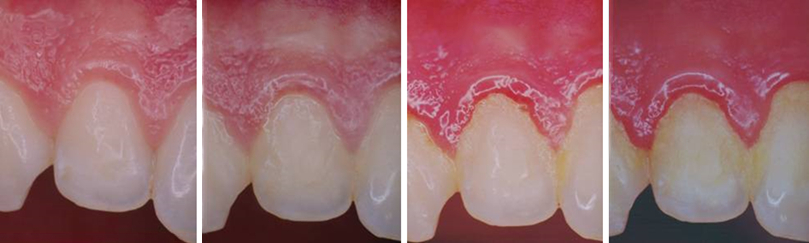

¿Cuáles son las etapas de la enfermedad de las encías?

La enfermedad de las encías es una inflamación de las mismas que puede avanzar hasta afectar el hueso que rodea y sostiene a los dientes